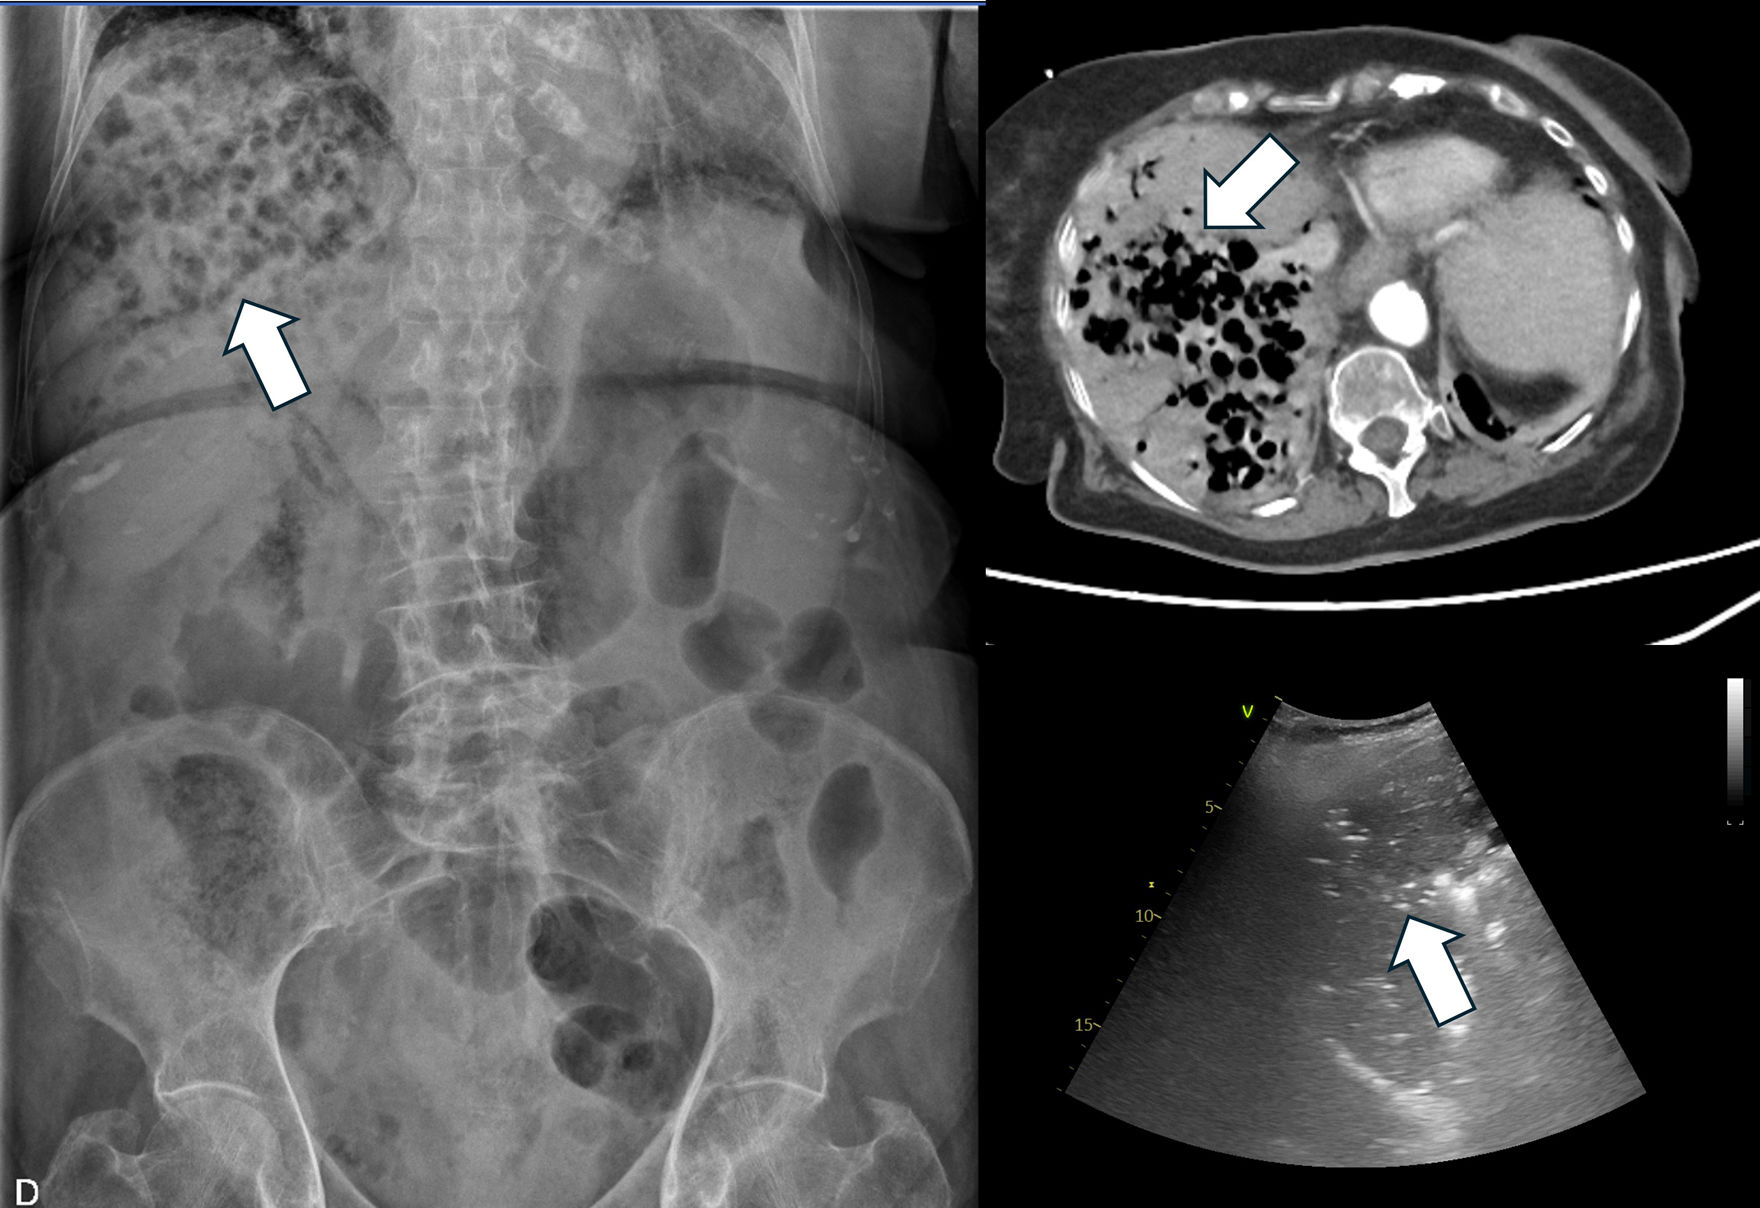

Se describe el caso de una mujer de 96años con diabetes y anemia ferropénica que acudió por dolor abdominal, vómitos oscuros y mal estado general. Presentaba febrícula, taquicardia, livideces cutáneas, defensa abdominal y peristaltismo ausente. La analítica evidenció acidosis metabólica, lactato elevado, aumento de transaminasas y bilirrubina, leucocitosis y proteínaC reactiva elevada. Como se puede ver en la figura 1, la radiografía, la ecografía y la tomografía computarizada mostraron abundante gas en el parénquima hepático (flechas blancas), confirmando el diagnóstico.

El hallazgo clave es la sustitución difusa del parénquima hepático por gas, sin efecto de masa ni colección líquida, con vasos hepáticos y porta permeables y sin gas intravascular, lo que la diferencia de otras entidades. A pesar de antibióticos de amplio espectro, drenajes y tratamiento intensivo, todos los casos reportados, incluida esta paciente, tuvieron desenlace fatal en 24-72horas. No existe un tratamiento eficaz establecido.